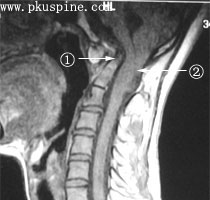

3、MRI檢查MRI是診斷本病最好的檢查手段之一,尤其在矢狀位可清楚的顯示中腦水管第四腦室及腦幹的改變小腦扁桃體下疝的程度及頸髓受壓的情況便於決定手術治療方案

部分患者延髓壓迫主要來自腹側面的枕大孔前緣向後移位的樞椎齒狀突,主要表現為錐體束損害,在MRI檢查的矢狀位上可以明確地看到壓迫來自腹側,這樣只做後枕部減壓無明顯效果,可以經頸部或口咽部前入路行減壓術,去除枕大孔前緣寰椎前弓和齒狀突手術中不打開硬膜,以防止腦脊液漏,對於腹側受壓的患者可取得良好的效果對於寰椎區穩定性差的患者在前入路手術後還需再行植骨融合術。